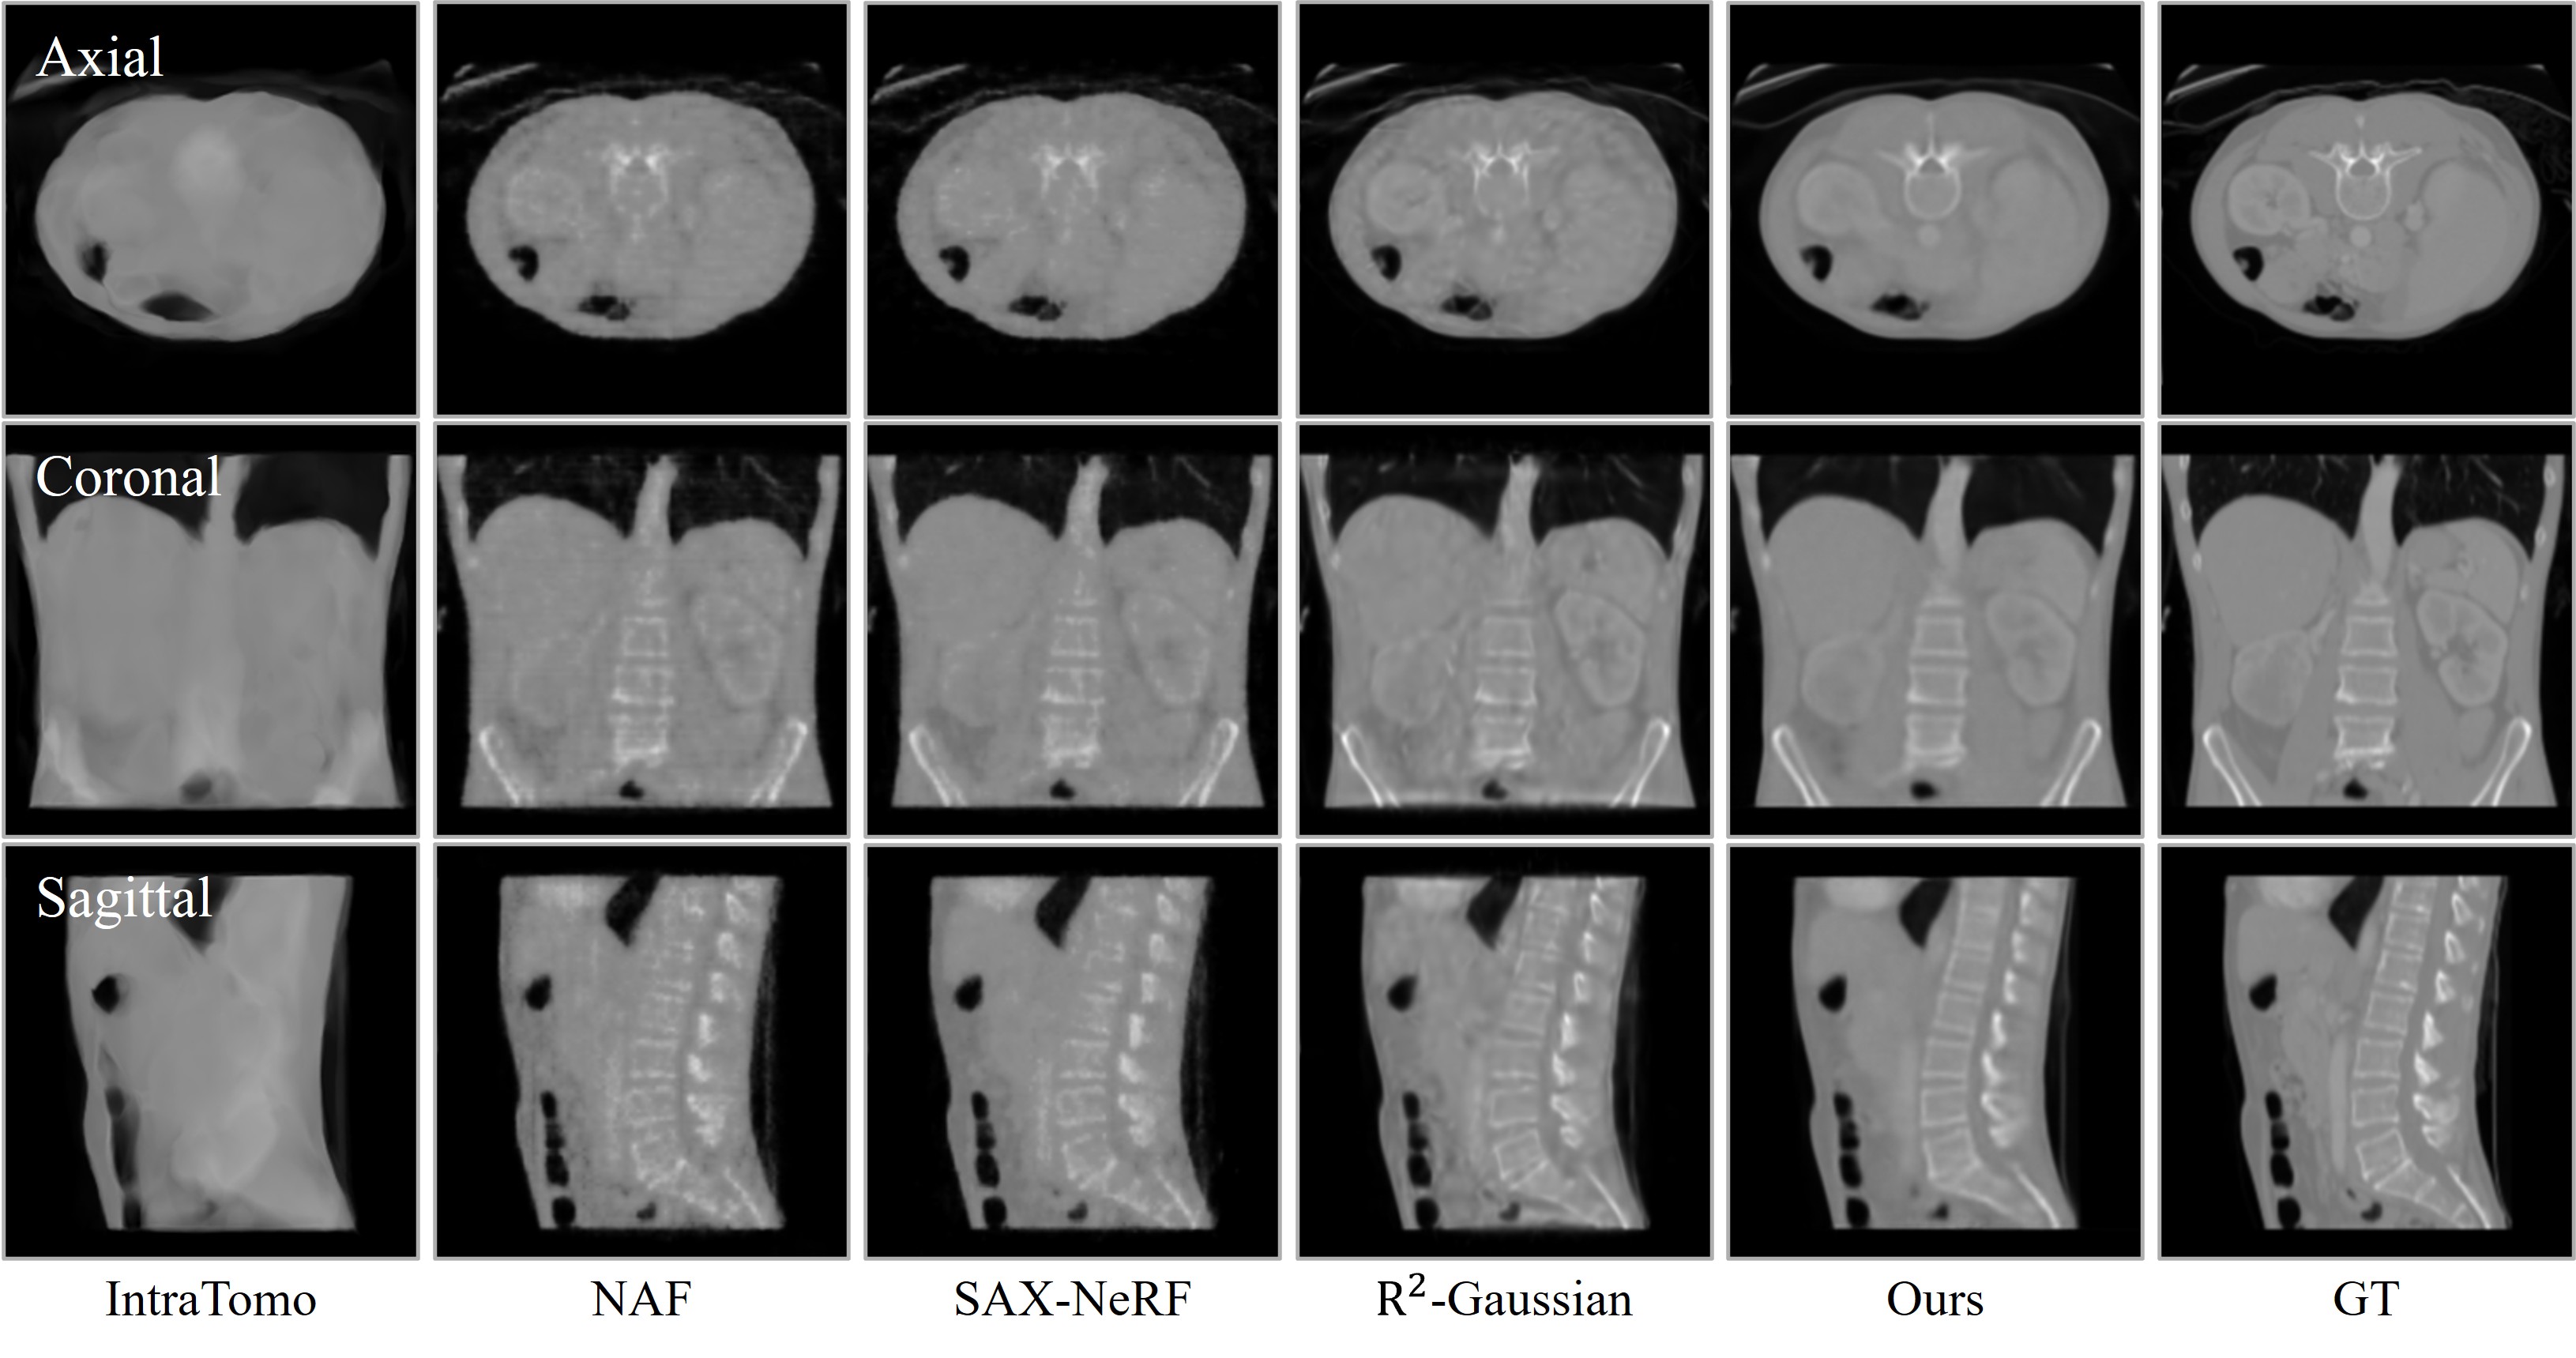

Visual comparison of CT reconstruction across different views. ILV achieves significantly cleaner structural details and consistency under both 10-view and 24-view sparse settings compared to existing methods.